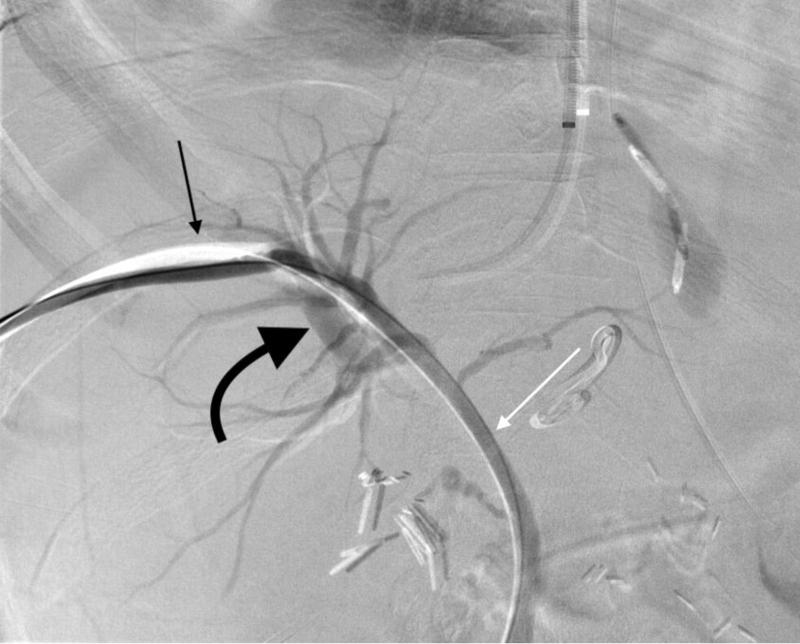

PTBD đường mật là gì và một số thông tin cần biết về PTBD đường mật

PTBD đường mật là một phương pháp can thiệp giúp dẫn lưu dịch mật khi đường mật bị tắc nghẽn, thường do sỏi mật, khối u hoặc các bệnh lý khác. Phương pháp này đóng vai trò quan trọng trong...